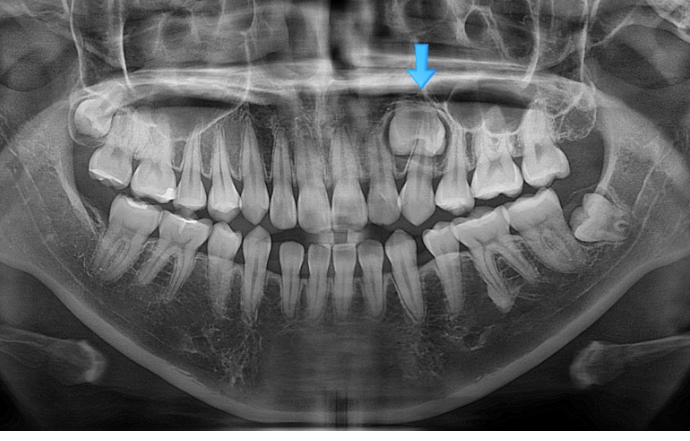

23.01

파란 화살표 자리에 있어야할 첫번째 작은어금니는 어디로 갔을까요?

네 매복이 되어있습니다.

매복치를 빼야만 교정이 가능한 경우도 많습니다. 하지만 이 매복치의 경우 매복깊이가 상당히 깊어 합병증이 우려가 되는 바 인접 치아들이 매복치를 건드리지 않게 치료계획을 세우기로 합니다. 다행히 매복치가 있는 좌측은 치아이동이 크게 필요하지 않습니다.

아래에도 첫번째 작은어금니가 양쪽에 각각 결손되어 있네요. 그래서 공간들이 남아 치아들이 벌어져 있습니다.

태어날때부터 없는 치아를 선천적 결손치라고 합니다.

결론적으로 작은어금니 4개 중 3개가 입안에서 안 보이는 상태입니다. 2개는 결손, 한 개는 매복.

23.01~25.07

2년반 교정기간동안 매복치는 건드리지 않았고 그대로 잘 남아있습니다.

치근평행도는 좋습니다.

2년반의 기간동안 치근흡수는 일어나지 않았습니다.